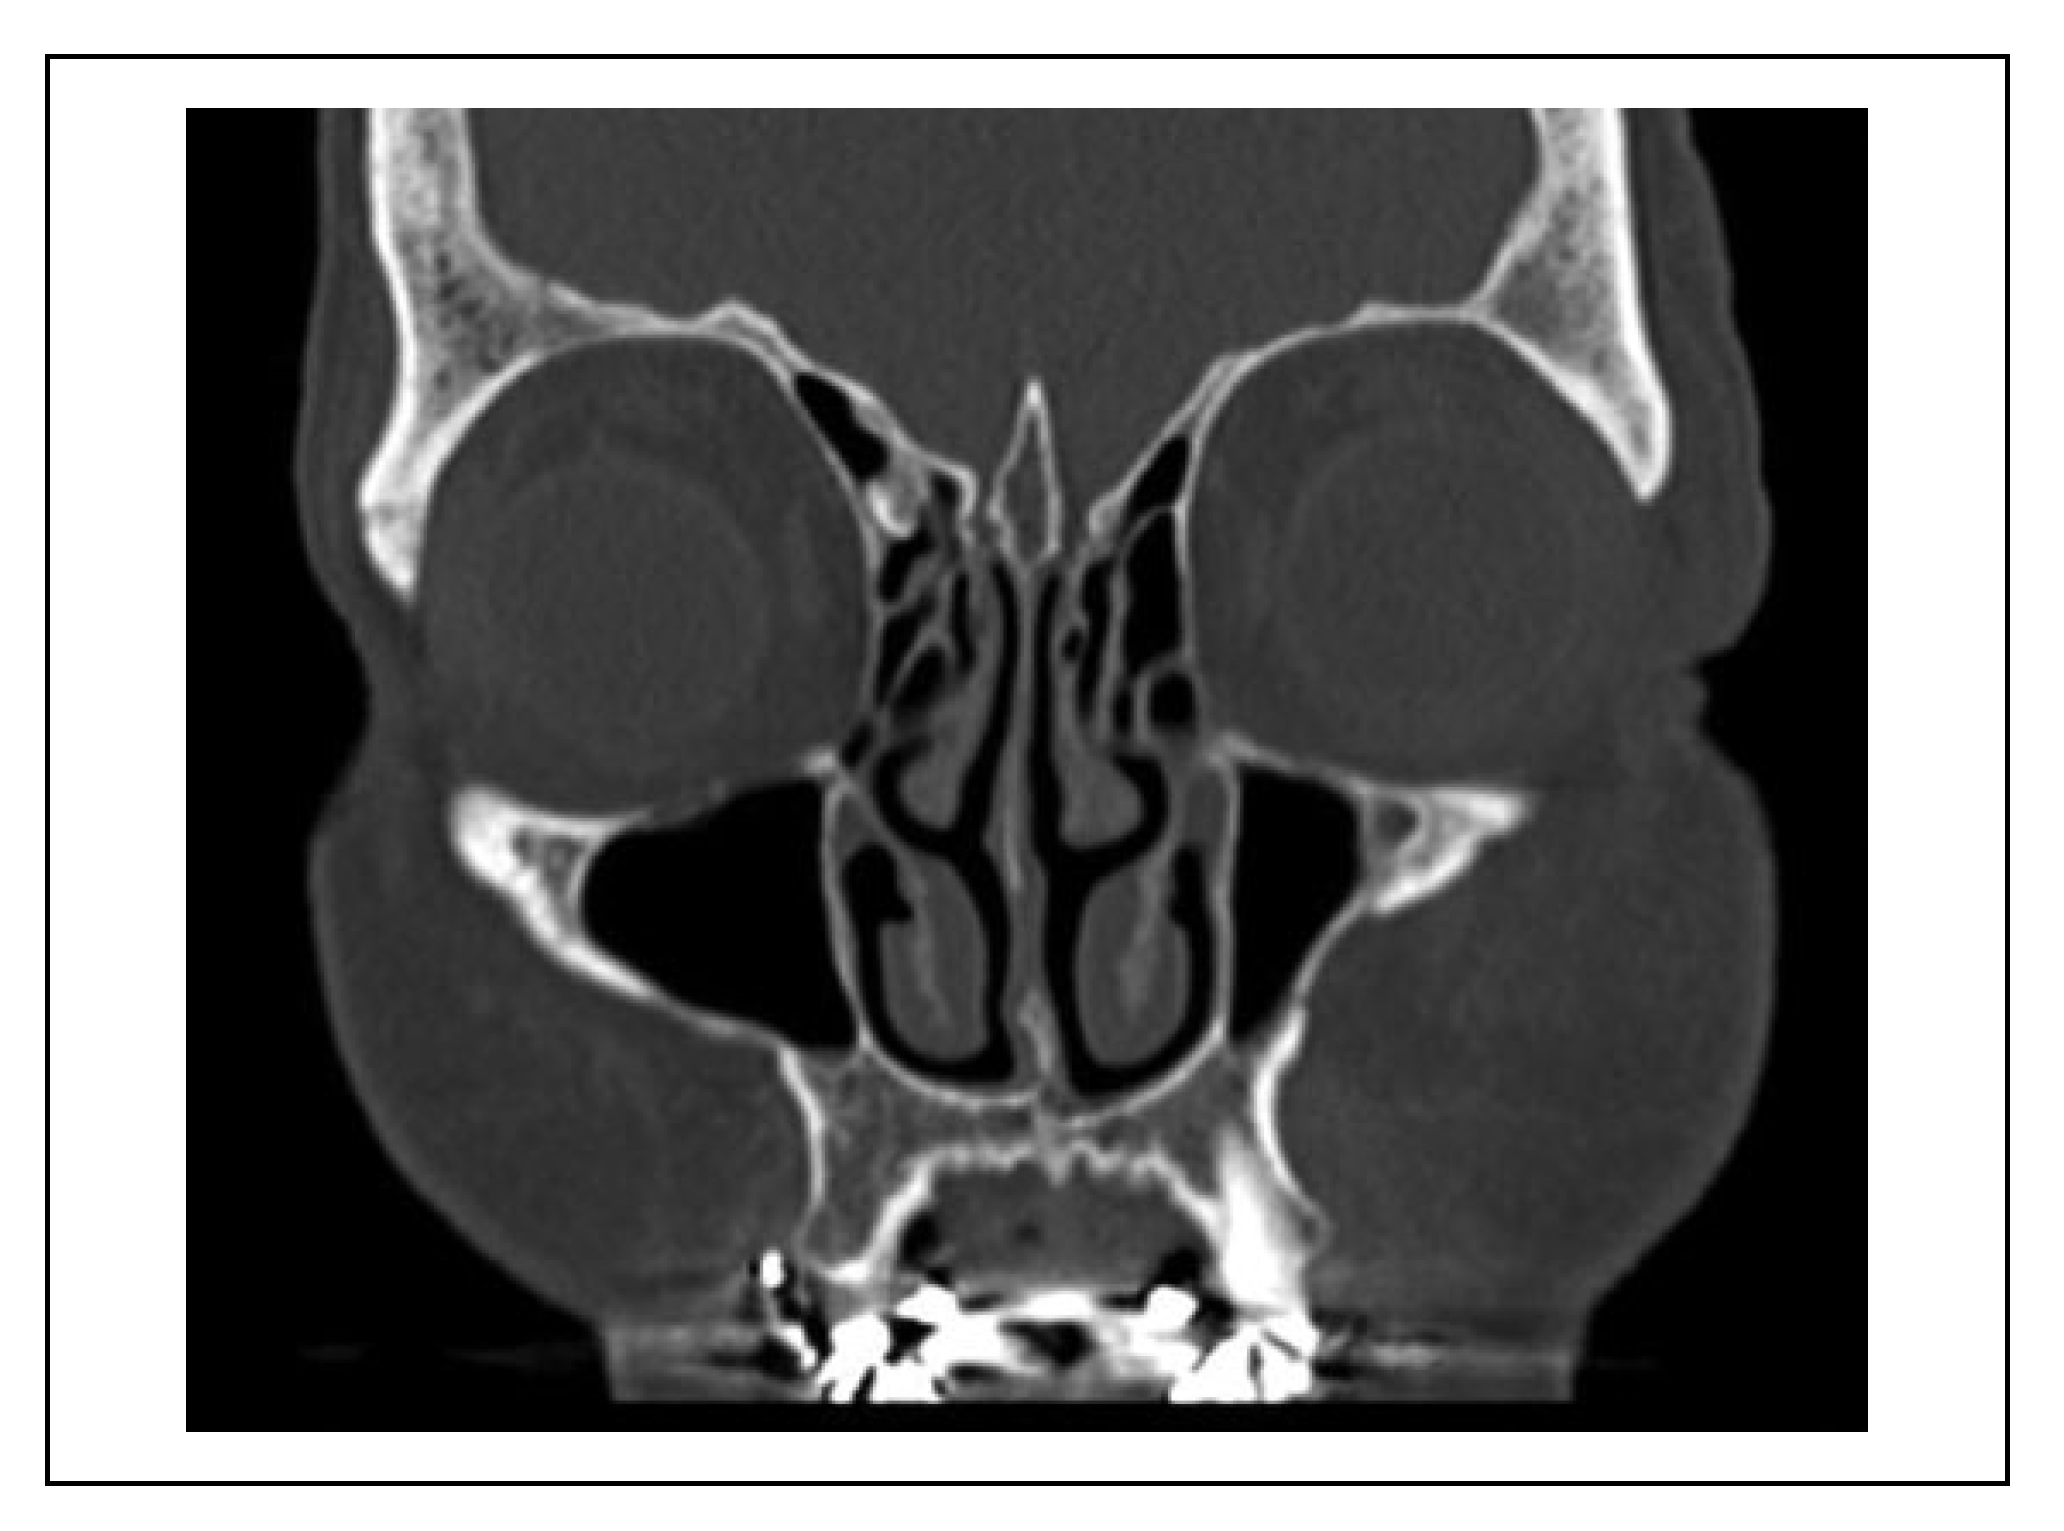

A case was considered to show involvement of the fracture course through the infraorbital canal (IOC) when the fracture line penetrated the cortex of the IOC at one site or more (Figure 2). When the fracture line was near the IOC (within 1 mm), this indicated that the cortex of the IOC was still intact (Figure 3).

Figure 2. Patient with a left zygomaticomaxillary complex fracture with the fracture line through the infraorbital canal and penetration of the cortex of the infraorbital canal. This patient experienced hypoesthesia of the infraorbital nerve.